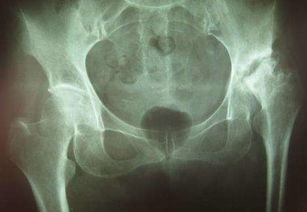

股骨頭壞死,又稱股骨頭缺血性壞死,為常見的骨關(guān)節(jié)病之一。

大多因風(fēng)濕病、血液病、潛水病、燒傷等疾患引起。至于它用什么方法治療比較好,這要看而定者的股骨頭的塌陷程度。